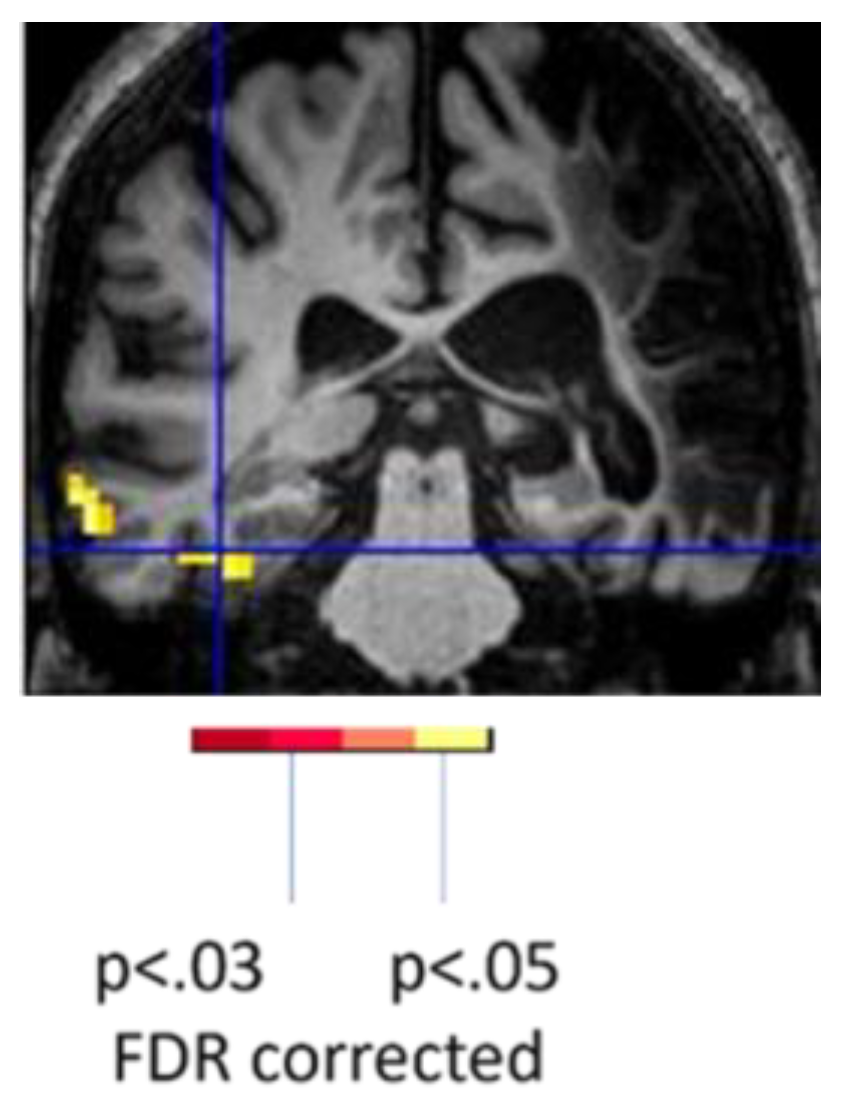

To illustrate the effect of language task, the woman described earlier who showed only left occipital activation with spelling showed bilateral activation and more left perilesional activation during reading (silent reading of words versus viewing of scrambled letter strings). (Figure 4) She read the words with 100% accuracy outside of the scanner that day. Her activation with reading was essentially the normal pattern seen in neurotypical controls [31.] While it might be tempting to conclude that the minimal activation of perilesional tissue during spelling was due to diaschisis, there was no evidence of diaschisis during the reading task the same day [27].

Figure 4. Task-related fMRI activation at Day 3 (acutely) post-stroke in the same woman associated with spelling (80% correct; left) and reading (100% correct; right).